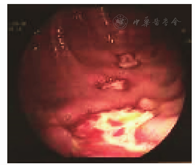

患者男,49岁。因"反复腹痛7年,加重1年"于2017年12月14日收入北京协和医院。患者自2010年起反复出现脐周胀痛,间断可见肠型,伴呕吐、排便排气减少等,每年发作3~4次。2017年初进展为持续轻度腹胀痛,间断加重,伴随症状同前,发作间隔数分钟至数小时不等,进食后加重,禁食、禁水后缓解。2017年3月患者腹痛再发时行立位腹部X线平片检查,提示小肠梗阻。小肠增强CT检查示小肠肠壁节段性增厚、肠腔狭窄。胃镜和结肠镜检查未见明显异常。外院经口小肠镜(图1)检查示距幽门200~230 cm处小肠多发溃疡(0.5 cm×0.5 cm~1.5 cm×2.0 cm),中央色红、凹陷,部分基底可及少量白苔;病理检查示空肠黏膜慢性炎,可见炎性肉芽组织伴大量淋巴细胞和浆细胞浸润。考虑为"IBD",口服美沙拉秦1 g(4次/d)和沙利度胺25 mg(2次/d)治疗3个月,腹胀痛未见好转。2017年11月行经肛门小肠镜检查,进镜至小肠距回盲瓣约120 cm,未见狭窄,回肠末段淋巴滤泡增生,小肠散在充血、糜烂斑;病理检查示黏膜慢性炎伴局部淋巴组织增生,黏膜固有层见较多中性粒细胞浸润。否认反复口腔溃疡、皮疹或关节痛;精神弱,睡眠欠佳。每日进食肠内营养粉约100 g,每周排黄褐色干便1次,每日排尿约1 000 mL。近1年体质量下降约10 kg。既往史:高脂血症,否认长期NSAID服用史,无腹腔手术史或外伤史。个人史、婚育史、家族史无殊。体格检查:腹膨隆,可见肠型,无压痛、反跳痛或肌紧张,叩诊呈鼓音,肠鸣音亢进。